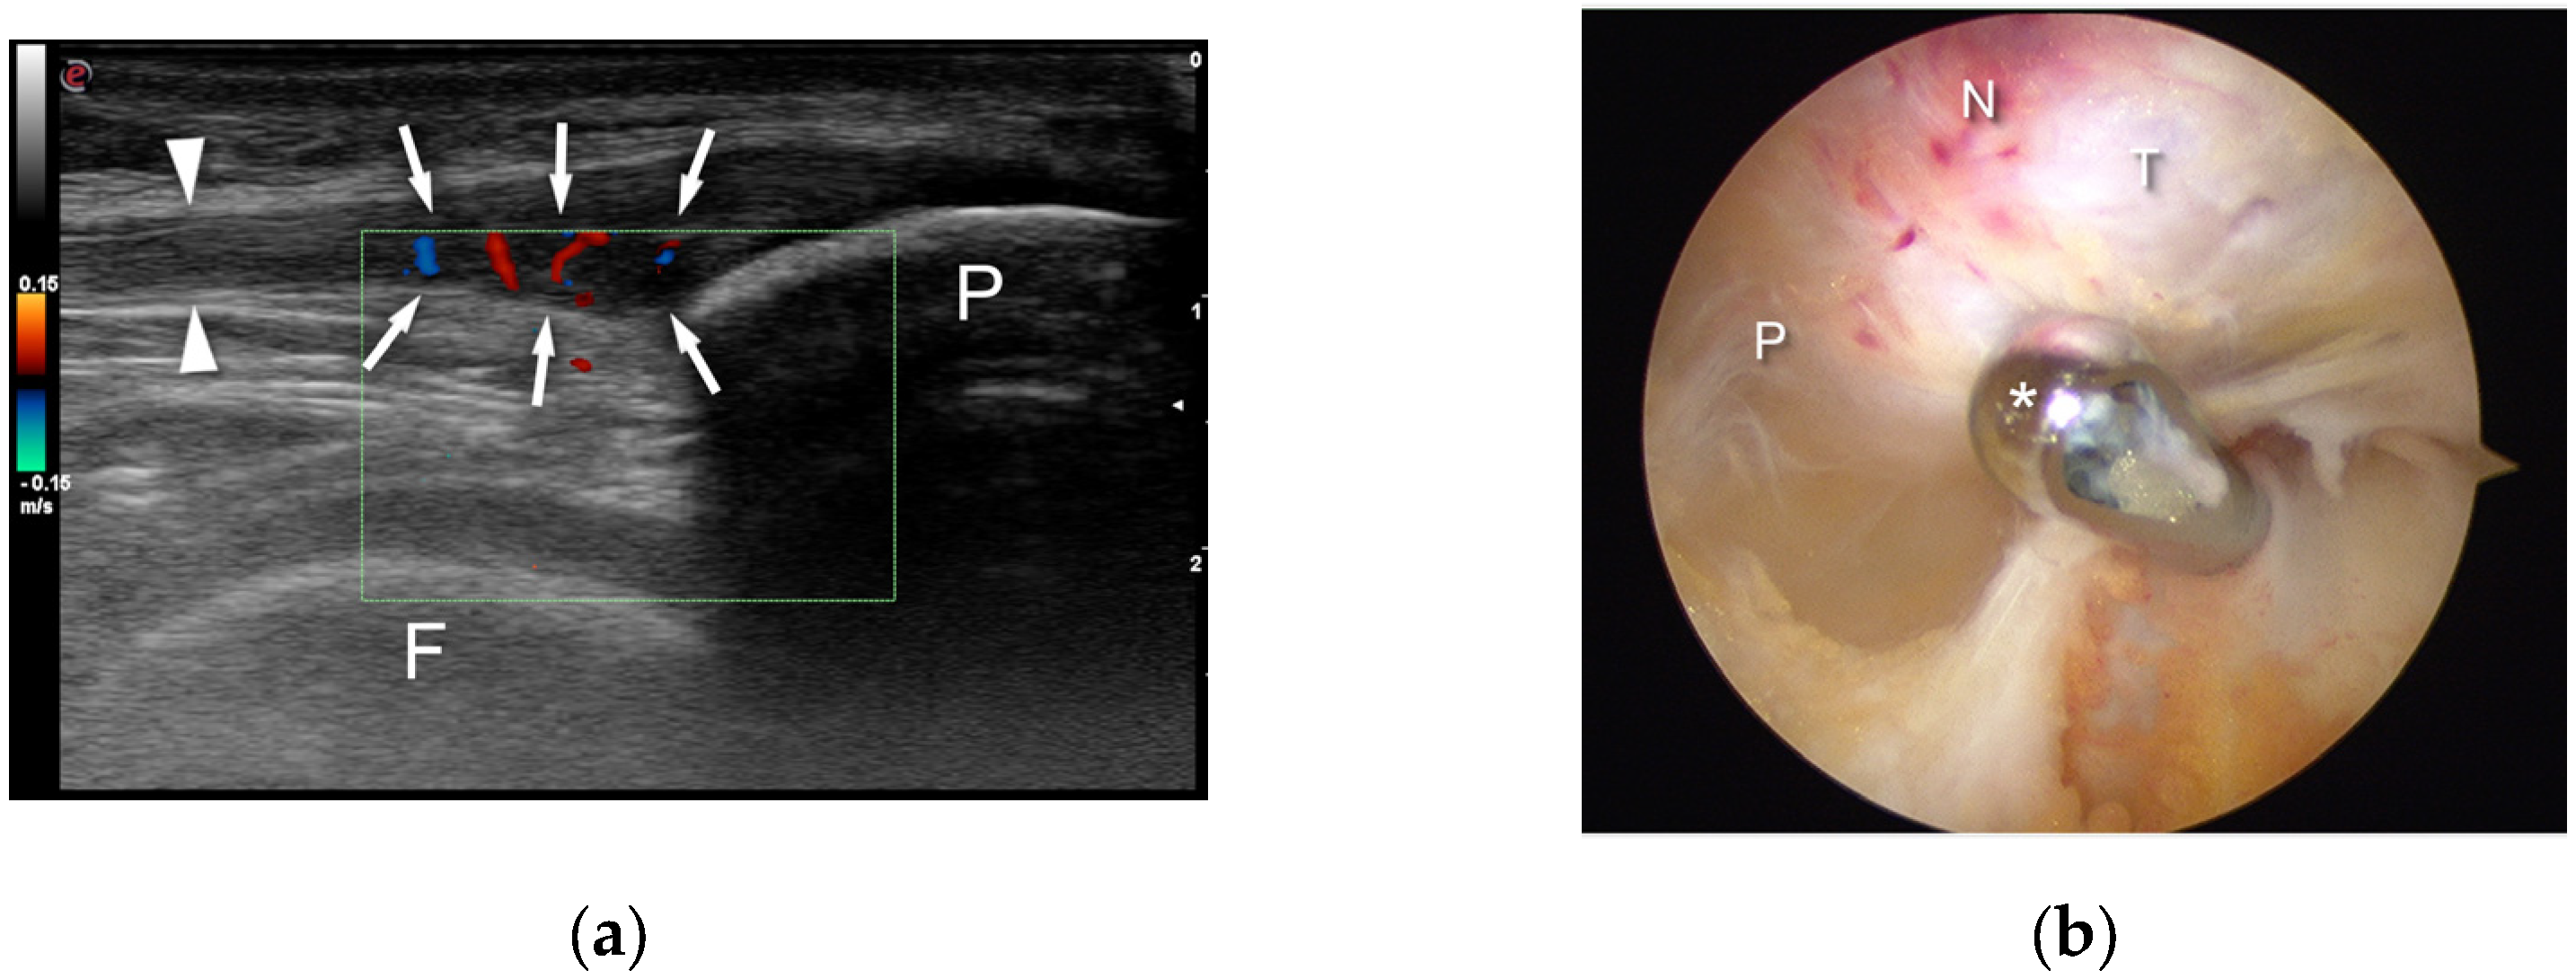

- Willberg, L.; Sunding, K.; Forssblad, M.; Alfredson, H. Ultrasound- and Doppler-Guided Arthroscopic Shaving to Treat Jumper’s Knee: A Technical Note. Knee Surg. Sports Traumatol. Arthrosc. 2007, 15, 1400–1403. [Google Scholar] [CrossRef]

- Sunding, K.; Willberg, L.; Werner, S.; Alfredson, H.; Forssblad, M.; Fahlström, M. Sclerosing Injections and Ultrasound-Guided Arthroscopic Shaving for Patellar Tendinopathy: Good Clinical Results and Decreased Tendon Thickness after Surgery—A Medium-Term Follow-up Study. Knee Surg. Sports Traumatol. Arthrosc. 2015, 23, 2259–2268. [Google Scholar] [CrossRef] [PubMed]